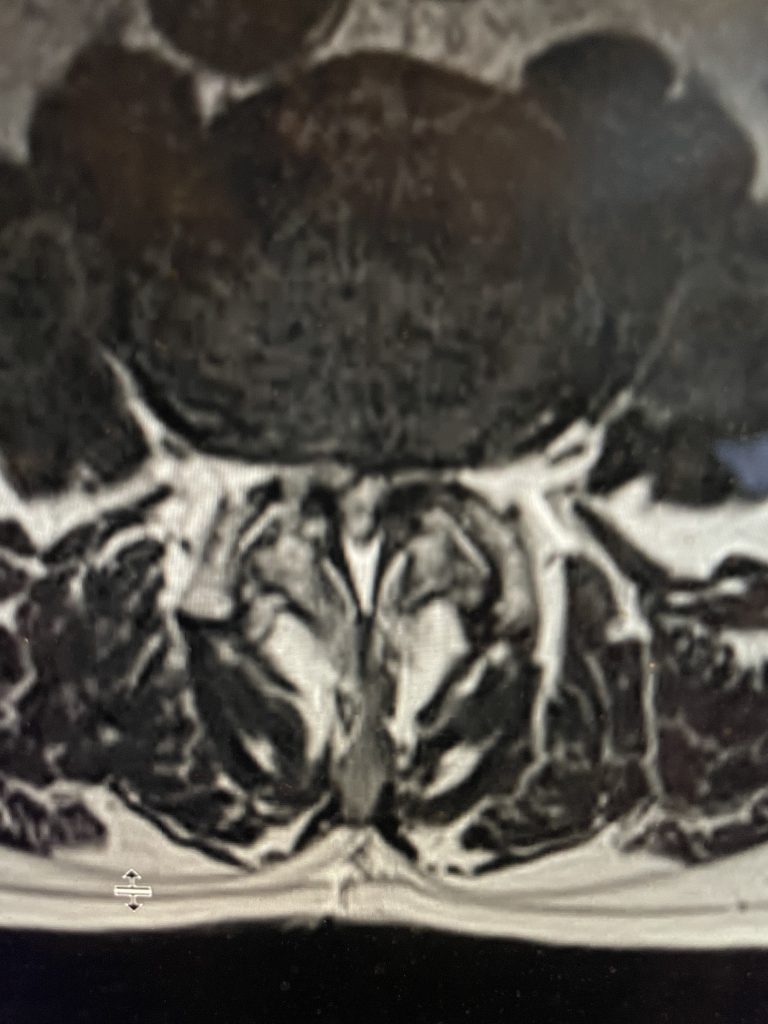

Here is a tough case: This is a 72 year-old male who presented with several months of progressive neck pain without symptoms of the arms or legs. […]